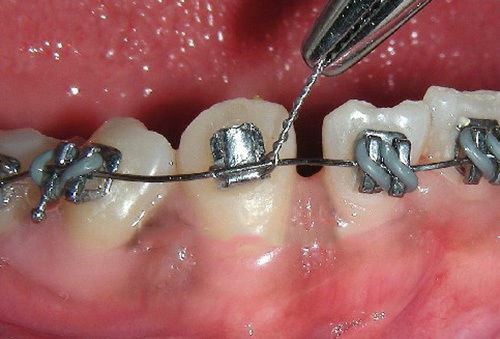

Le fil de ligature métallique en bobine est un instrument orthodontique indispensable pour les situations cliniques nécessitant une force de ligature élevée et un contrôle précis, notamment lorsque les ligatures élastiques classiques ne sont pas suffisantes. Conçu pour répondre aux exigences des traitements orthodontiques modernes, ce fil garantit sécurité, efficacité et polyvalence en cabinet.

Fabriqué en acier inoxydable recuit de haute qualité, le fil offre une souplesse exceptionnelle facilitant sa manipulation, son torsadage et son adaptation autour des ailettes des brackets, tout en conservant une résistance mécanique optimale. Cette combinaison permet d’obtenir une force de serrage maximale, assurant un maintien ferme et stable de l’arc orthodontique tout au long du traitement.

Sur le plan clinique, le fil de ligature métallique sur bobine est extrêmement polyvalent. Il est couramment utilisé pour la fixation sécurisée des arcs orthodontiques sur brackets métalliques ou céramiques, mais également pour la réalisation de contentions temporaires, de ligatures en “8” (Lace back) afin de solidariser un groupe de dents et prévenir l’ouverture d’espaces, ou encore pour la traction de dents incluses et d’autres mécaniques orthodontiques avancées.

Disponible en plusieurs diamètres (.008, .010, .012), ce fil s’adapte parfaitement aux différentes phases du traitement, du contrôle léger aux situations nécessitant une ligature plus rigide et plus puissante. Sa surface lisse et régulière contribue à réduire les irritations des tissus mous, assurant ainsi un meilleur confort pour le patient.

- Ligature forte et sécurisée des brackets (métalliques ou céramiques)

- Ligatures en « 8 » (Lace back) pour la fermeture et le contrôle des espaces